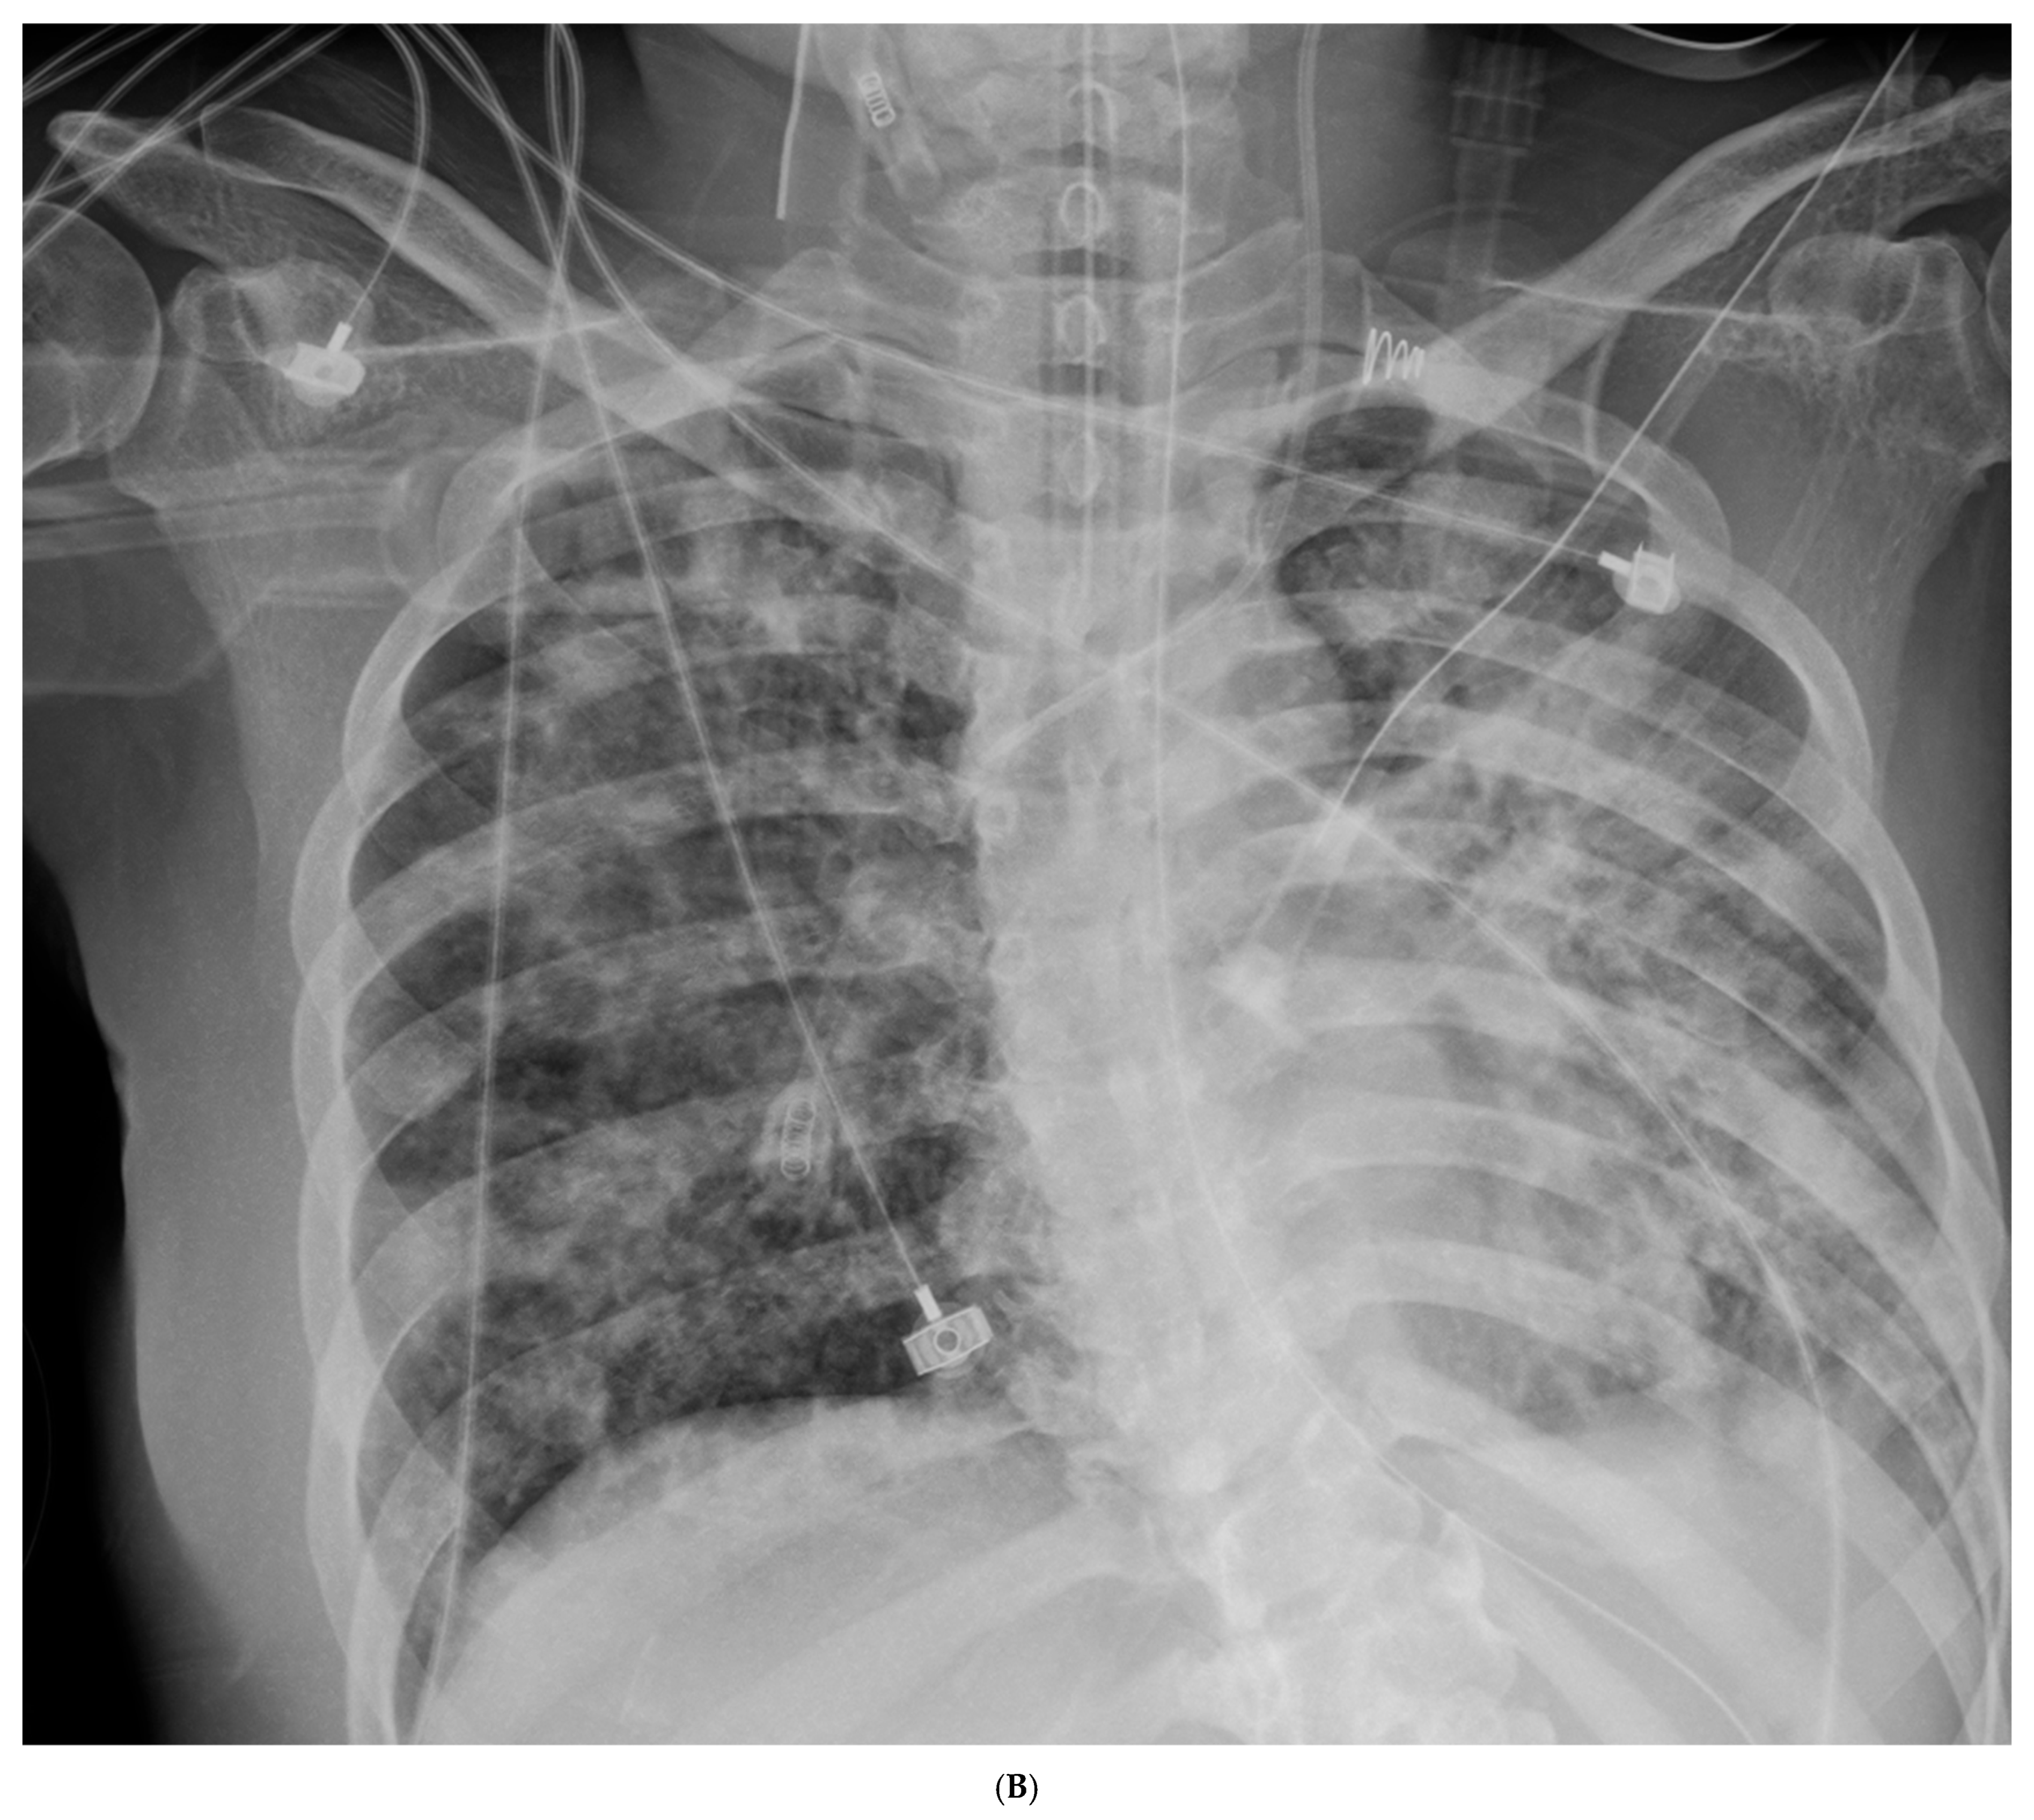

| 10 | VAP #1, change to TZP+Amikacin | 7.41 | 150 | 2.2 | 8.1 | MPD 40 | HREZ | TZP+Amikacin (inh) | No |

| 10 | VAP #1, abx change | TZP+Amikacin | P/F 150, CRP 22 |